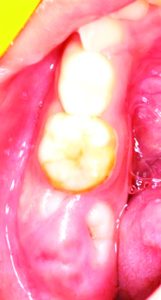

Consider the case of a 5-year-old patient whose lower second milk molar was affected by a condition known as Molar Hypomineralisation. The tooth was filled to address the decay.

The Positive Outcome: Two years later, the permanent molar erupted in its intended position behind the same. This early intervention prevented the decay from impacting the alignment of the permanent teeth. If the milk tooth had not been treated, the space left by the decay could have caused the permanent molar to erupt improperly, potentially leading to future orthodontic issues and the need for braces.